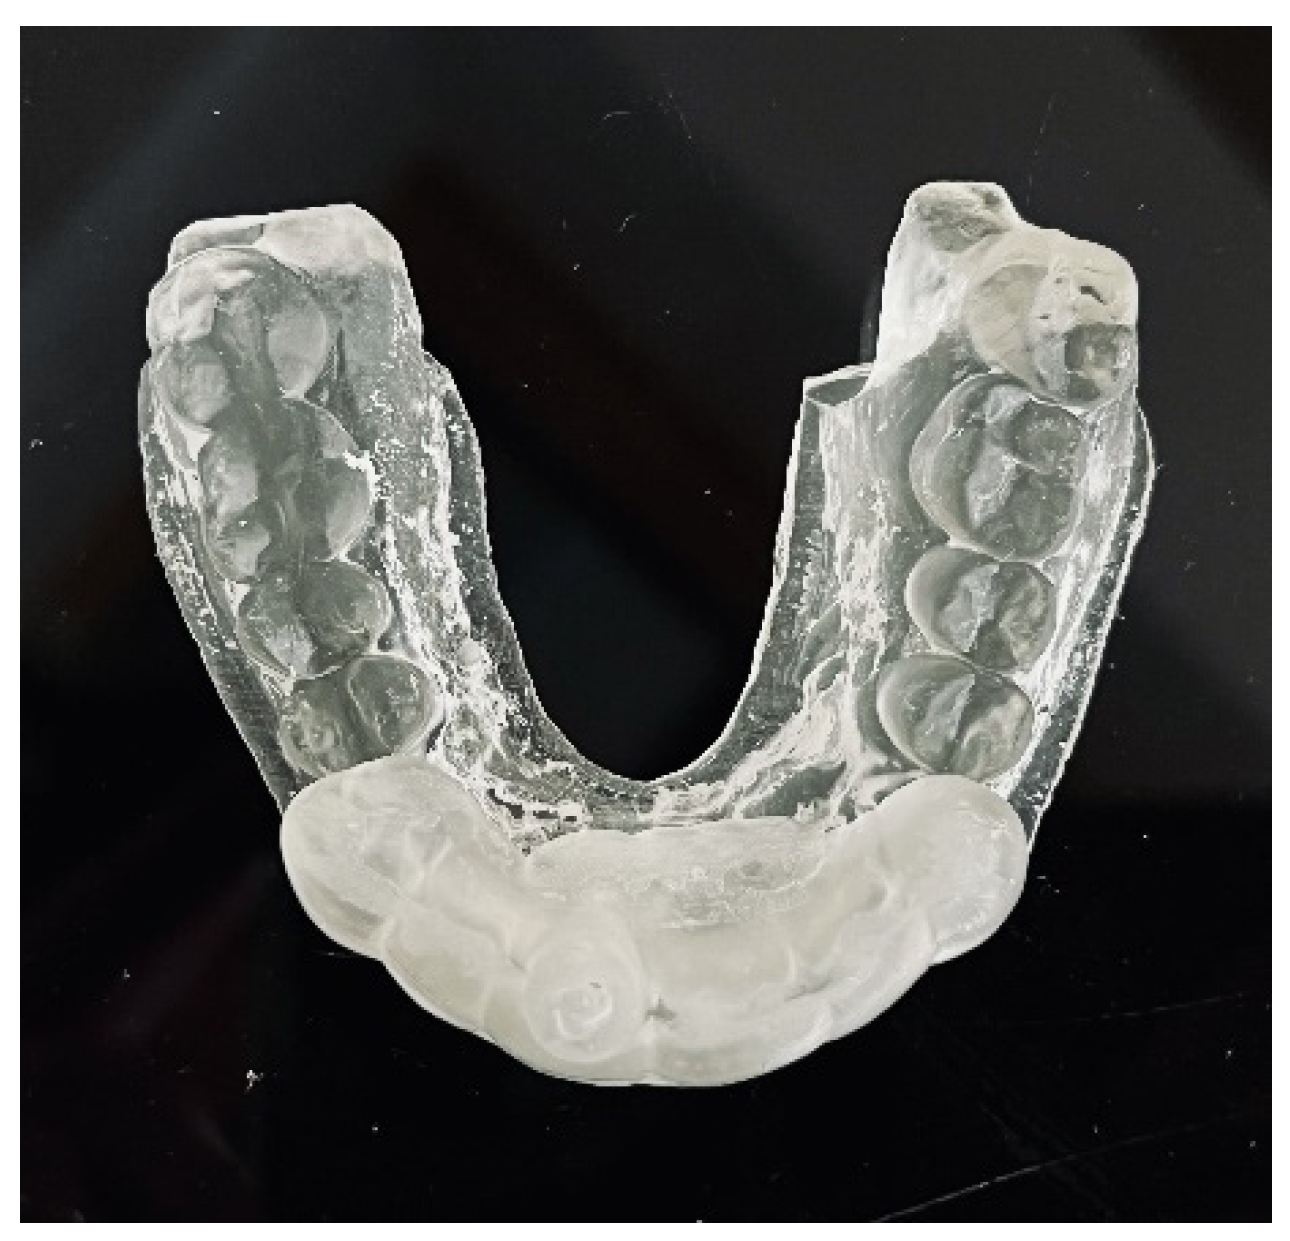

As in the previous case, the virtual drill orientation was established in the centre of the root. The top of the sleeve was 14 mm from the bottom of the tooth chamber. The guide sleeve was 6 mm long and 1 mm in diameter (Figure 26). The template with engraved canal markings was equipped with a window for assessing the correctness of the guide’s intraoral placement (Figure 27). The buccal canal was cautiously negotiated through the guide with a size 10 file (C-Pilot #10) instead of rotated burs. The root canal orifice was reached at a length of 15 mm from the top of the guide sleeve. The time needed to localize the canal path in this case was approximately 10 min. The file was taken to the working length and a conventional root canal treatment followed (Figure 28).

Figure 27. Image presenting guide with window on the occlusal site that allowed us to check the correctness of the endodontic guide placement.